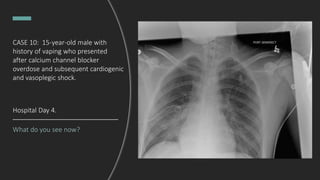

Hospital Day 4.

CASE 10: 15-year-old male with

history of vaping who presented

after calcium channel blocker

overdose and subsequent cardiogenic

and vasoplegic shock.

Pigtail chest tube inserted and pleural

effusion drained.

Hospital Day 4. BAL grew

MRSA, antibiotics changed to

vancomycin.